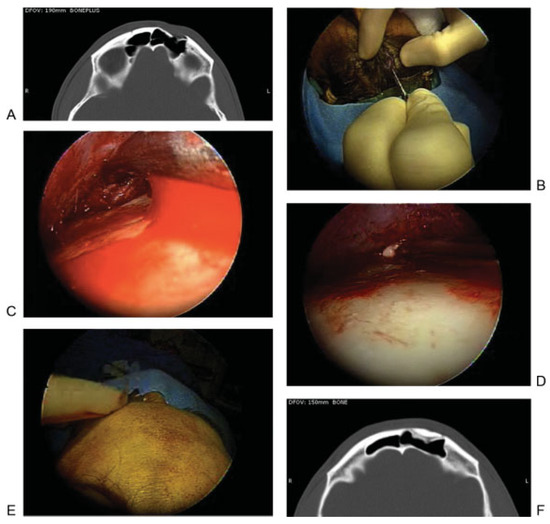

Figure 2.

Trephination approach for endoscopic assessment of the posterior wall. (A) Incision. (B) Exposure of fracture. (C) Exposure of sinus. (D) Exposure of posterior wall of frontal sinus. (E) Repair.